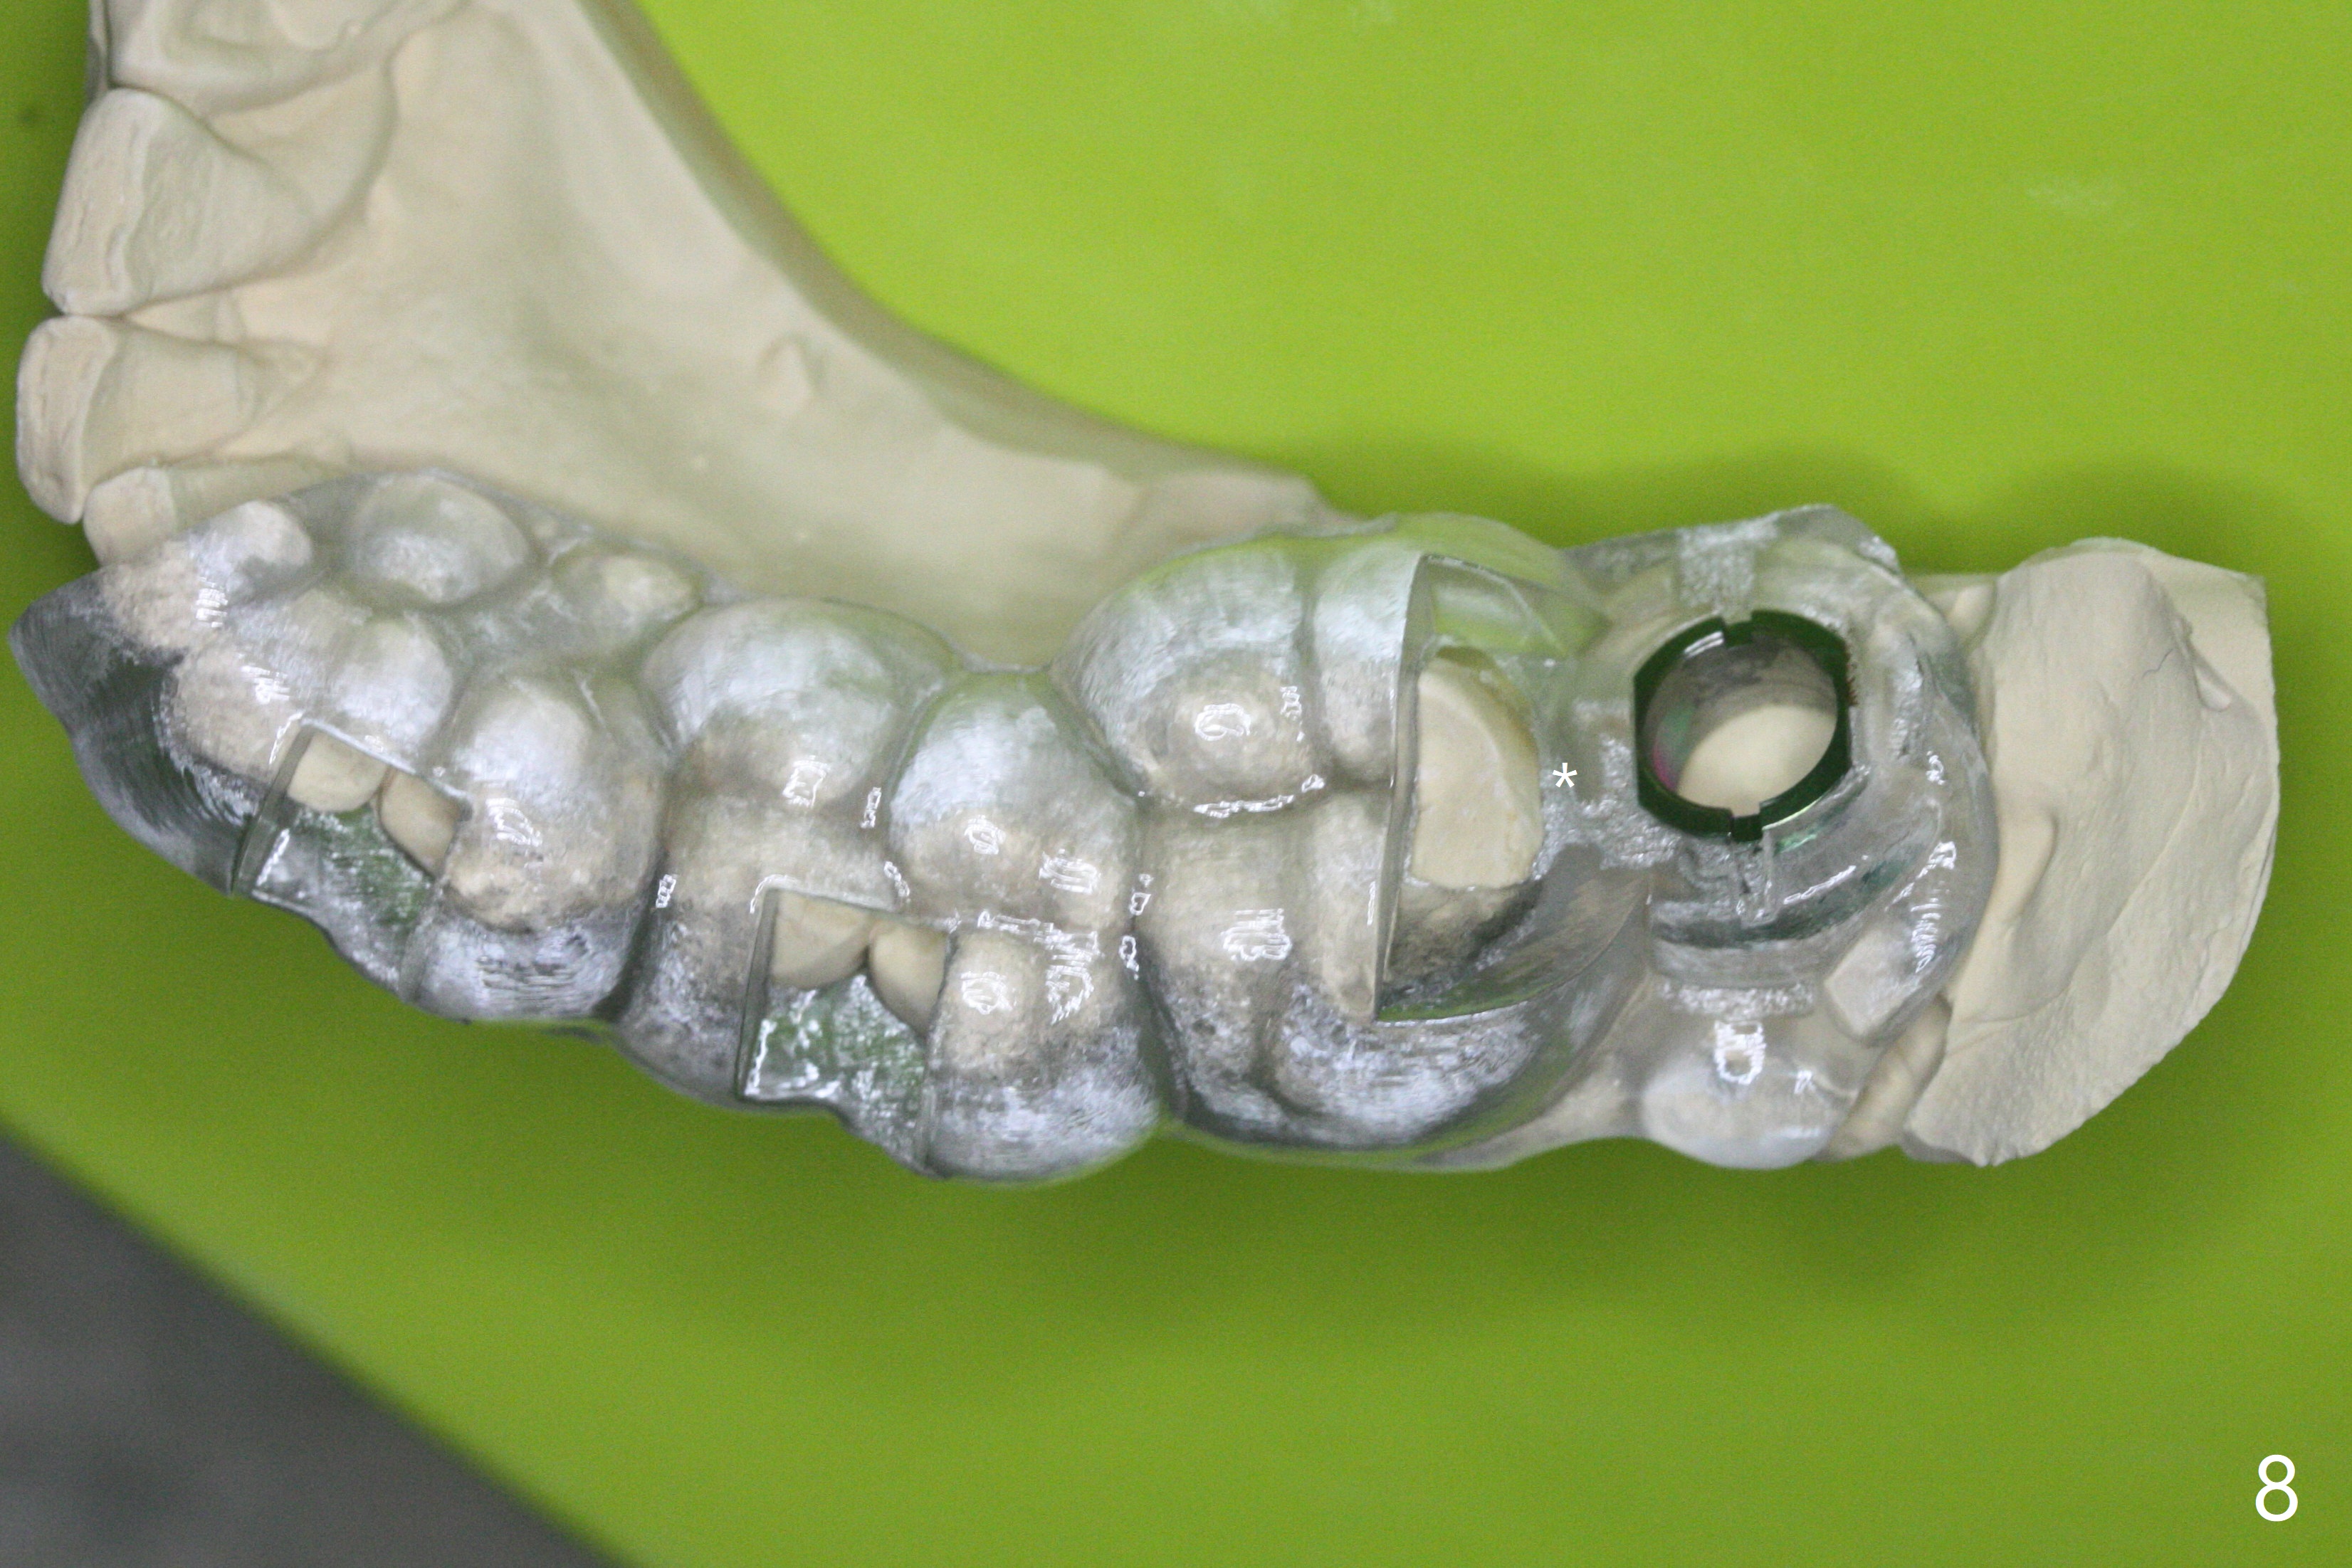

病人回来左下7拔牙植牙,十分感激导板取模后松动牙固位(图一),让他能正常吃饭。去除颊侧树脂和钢丝,6,7之间树脂自动脱落。拔牙后,肉芽组织很多,需要把局麻药注射至肉芽组织中,刮除时不慎远中舌侧牙龈穿孔。尽管纱布压迫,渗血相当多。怀疑导板就位不全,没有纠正。完成钻洞,报废植体无法就位。放置最后一个钻头,根尖片显示钻洞太浅了(图二)。再次磨除6颊侧,远中树脂,导板好像就位,重复钻洞,仍旧太浅(图三),CT表明钻洞偏颊侧(图四)。准备徒手改变钻洞,但是病人疼痛,只好植骨(粘性骨粉)(图五),牙槽窝舌侧,咬合面各覆盖一张PRF膜(图六:箭头),牙间隙维持器和牙周敷料固定。导板在曾经有树脂地方必须缓冲(图七:6;八:*,与图一对比),磨除深度有时不准确。术后两周牙周敷料仍稳定(图九),虽然病人希望撤除,我们偏向保留。反正病人正在做局部牙齿矫正。术后三周牙周敷料脱落,左上6咬合面树脂为了对侧局部牙齿矫正(图十)。骨粉有些丧失(图十一),最好手术时使用不可吸收膜。术后四个月牙槽窝充满骨粉,可以在下齿槽管颊侧植入4x8.5毫米植体(图十二)。